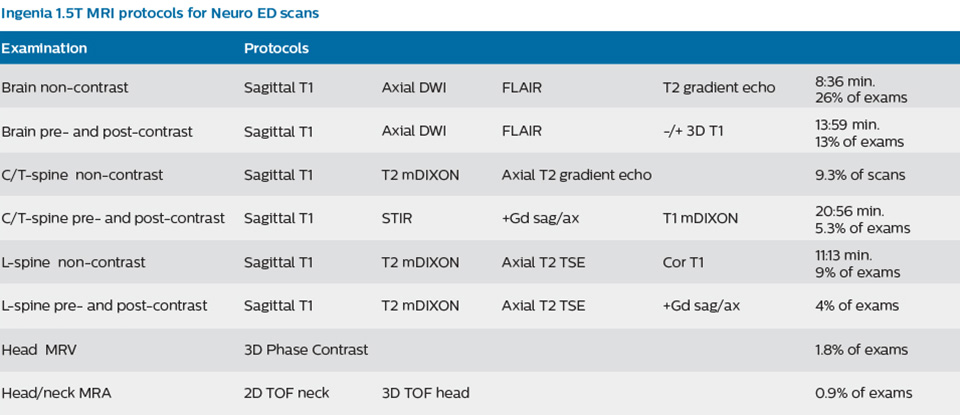

In order to address efficiency, matched with state-of-the-art capabilities to support a rich diagnosis, the decision was taken to include a Philips Ingenia 1.5T MRI scanner with wide bore in the new setup of the ED to enable scanning of virtually all patients.

To minimize the time taken to perform scans, rapid MRI examination protocols (ExamCards) were developed, shortening the total scanning time to even less than 10 minutes in some exams. Techniques like mDIXON (modified DIXON) are used for robust capturing of fat-free MRI images in a hectic ED environment.

A range of protocol sheets was developed to help ensure that referring physicians order the most appropriate MRI exam. The optimized MRI protocols also include 3D contrast-enhanced imaging, allowing neurosurgeons to comfortably use the isotropic data in the operating room while performing stereotaxic surgery.

The ED physicians can only request exams from a selected set of available exam protocols – as represented on the protocol sheet – minimizing the time necessary for the MRI scan. The sheet contains advice as to which scan to order (i.e. MRI vs. CT, contrast vs. non-contrast) depending on the situation, and encouraging physicians to order targeted scans. Even though the process has now been implemented, education still remains important; new neurology residents, for example, are informed as to the use of the ED MRI scanner, how it’s being utilized, and the importance of targeted scanning. “In my opinion, education has been crucial to establish the MRI exam as an ED test,” says Dr. Karis. “This is really key. If you can’t establish this concept, then you can’t convert everyone to the mindset that this is an ED test.”